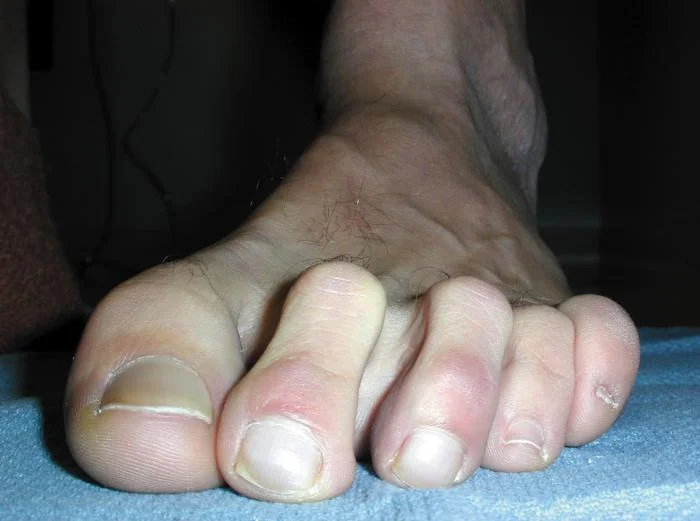

Hammer Toe

Lesser Toe Claw-Mallet-Hammer Toe

The toes have buckled making some of the joint prominent. This causes rubbing on the joints making them red and painful. Read more >>